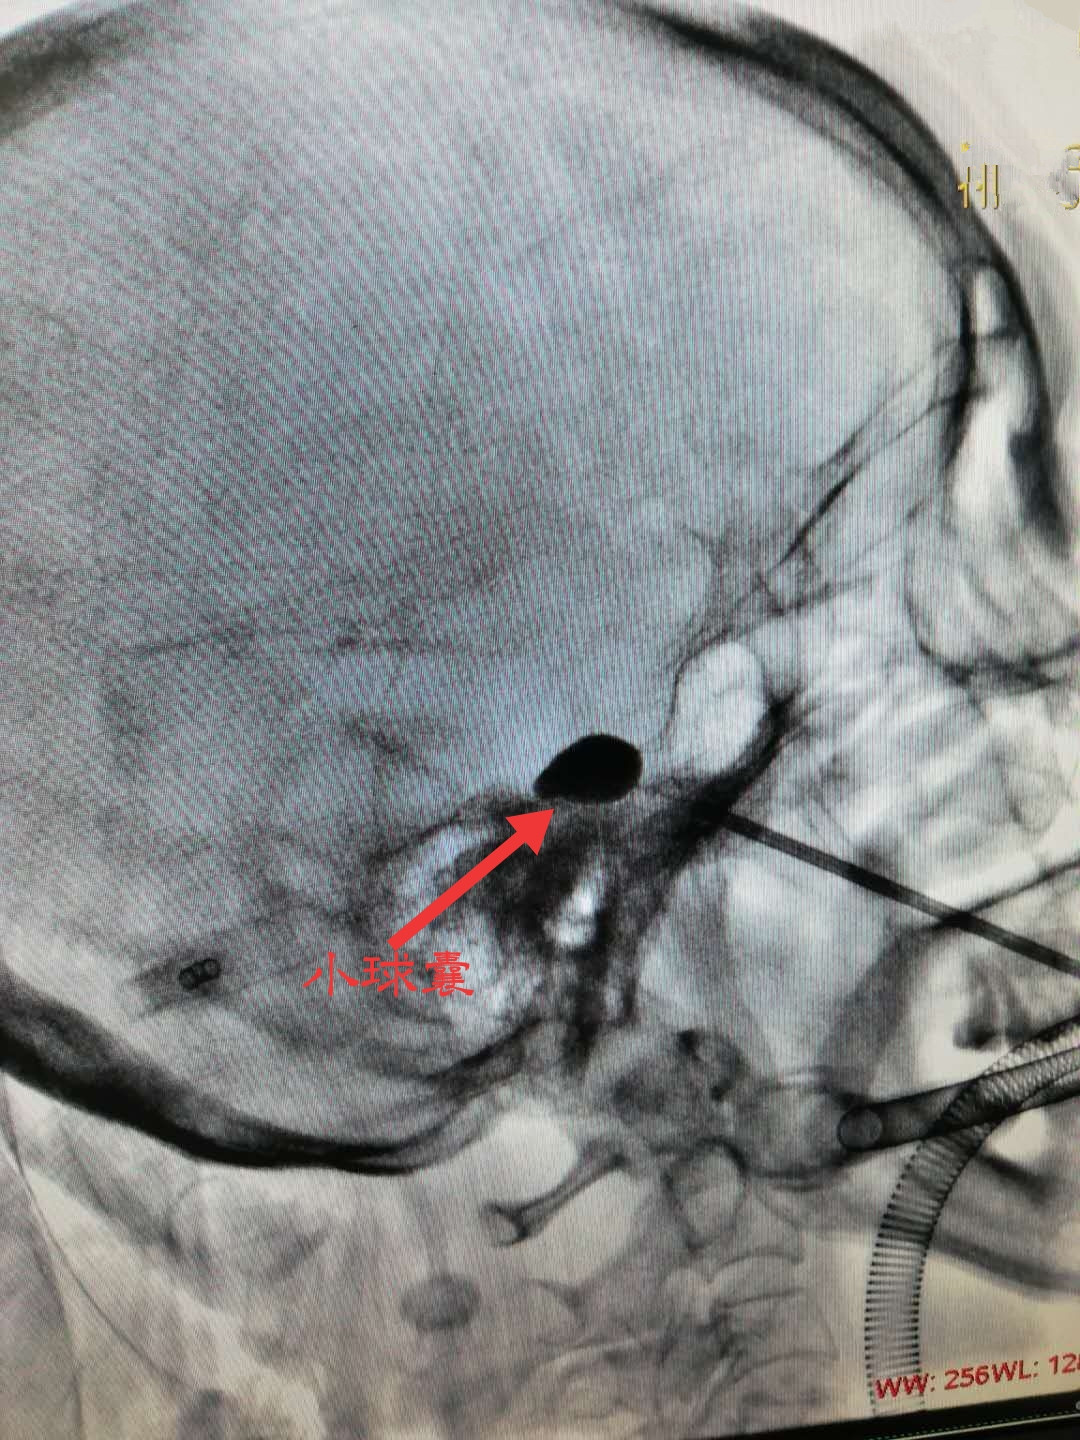

考虑到张阿姨身体基础条件差,一般的外科手术需要开颅进行身体恐难承受,人民医院疼痛科团队通过与张阿姨沟通并经家属的同意之后,决定避免开颅风险,采用“微球囊压迫术”进行治疗。张阿姨的微球囊压迫术历时不到30分钟,术后不仅疼痛感消失,吃饭、喝水、刷牙也不受影响。

微球囊压迫术是近年来治疗三叉神经痛的新手段,手术时患者全程无痛,平均手术时长为10~30分钟,避免了开颅手术可能存在的致残、致死等严重后果。(疼痛科 龙婷)